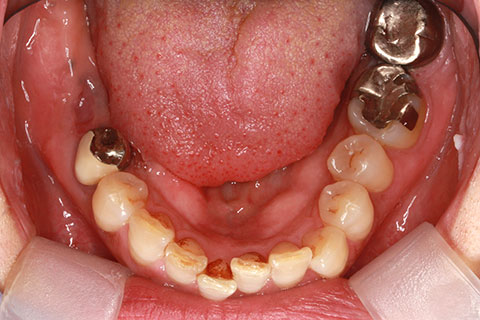

症例3

治療前

インプラント埋入時

治療後

- 年齢・性別

- 60歳男性

- 治療期間

- 2ヶ月

- 抜歯

- なし

- 治療費

- 61.6万円

- 備考

- 右下6.7欠損

- 治療内容

- 右下6.7欠損部にインプラント埋入

- 施術の副作用(リスク)

- オペによる知覚障害。インプラントによる歯肉炎。インプラント脱落。